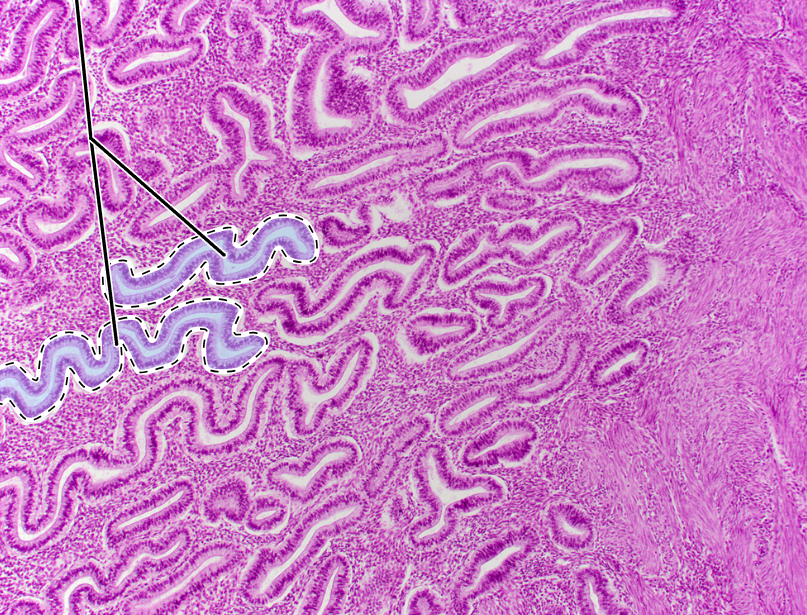

uterus

endometrium

uterine glands

myometrium